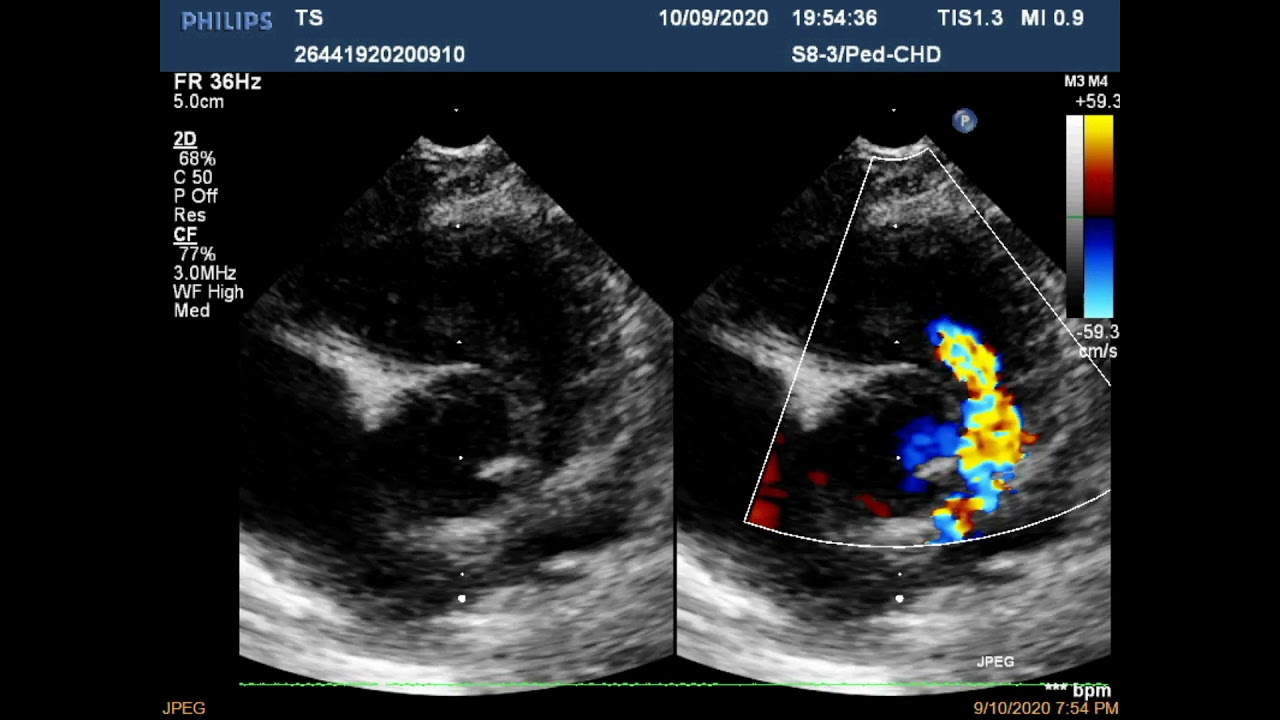

Одним из основных методов является эхокардиография, которая позволяет визуализировать структуру сердца и оценить его функции. С помощью ультразвукового исследования можно выявить аномалии, характерные для тетрады Фалло, такие как стеноз легочной артерии, дефект межжелудочковой перегородки и смещение аорты.

Важным аспектом является опыт и квалификация врача, проводящего УЗИ. Для более точной диагностики может потребоваться использование специализированных методов, таких как 3D-УЗИ или допплерография, которые позволяют более детально оценить кровоток и структуру сердца плода.

Диагностика тетрады Фалло включает физикальное обследование, аускультацию сердца, а также инструментальные методы, такие как эхокардиография, рентгенография грудной клетки и электрокардиография. Эти методы помогают выявить характерные изменения в структуре сердца и его функции.